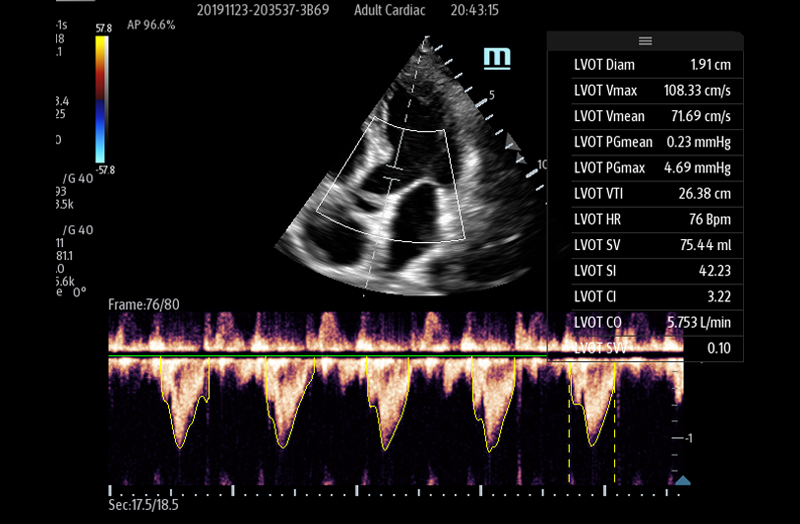

The TE7 Max Ultrasound System is designed to maximize your capabilities in demanding Point of Care environments. With its thoughtful industrial design and best-in-class image quality, the

TE7 Max provides a superior user experience during rapid clinical assessments and procedures taking place at the patient’s bedside

or on the go.

The TE7 Max boasts a large 21.5” vertically oriented high-definition display and a sealed touch-based interface to optimize visualization and accessibility when every second counts. The TE7 Max also incorporates a comprehensive suite of artificial intelligence (AI) powered Smart Tools and workflow enhancement software (iWorks™ Protocol) making efficiency and reproducibility the expectation for all end users.